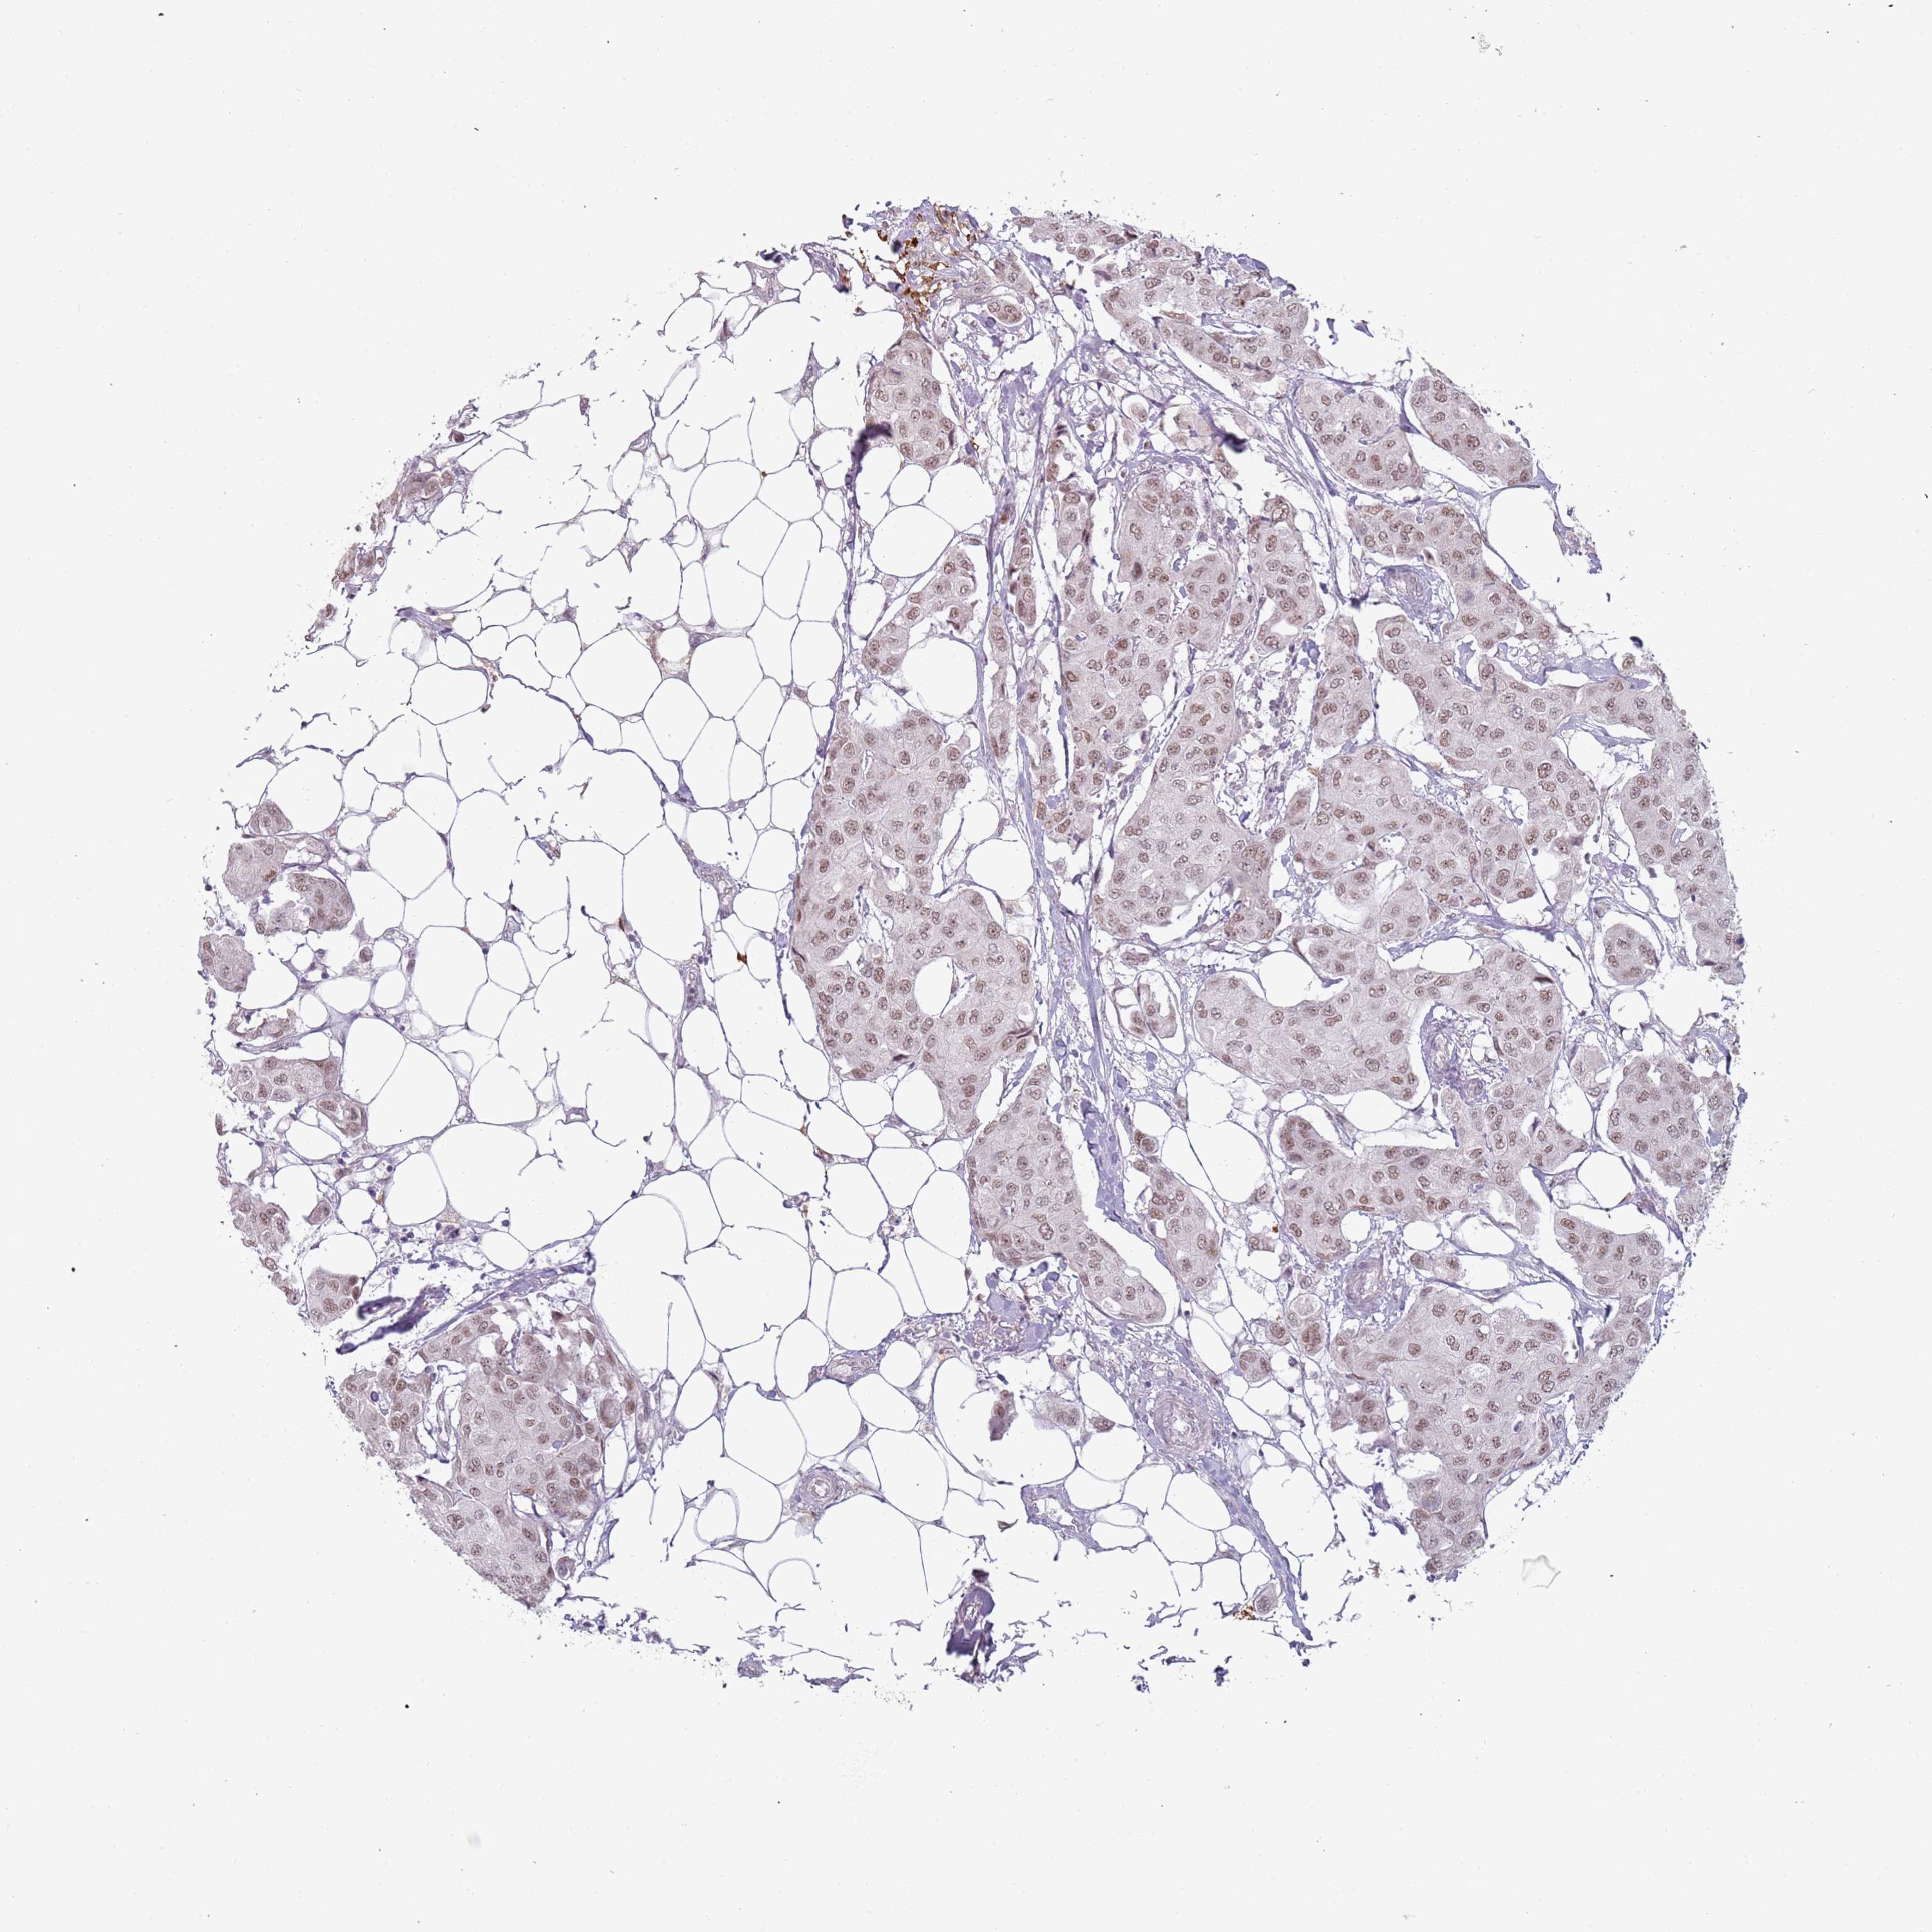

CANCER BREAST CANCER Show tissue menu

BRCA TCGA BRCA VALIDATION PROTEIN EXPRESSION